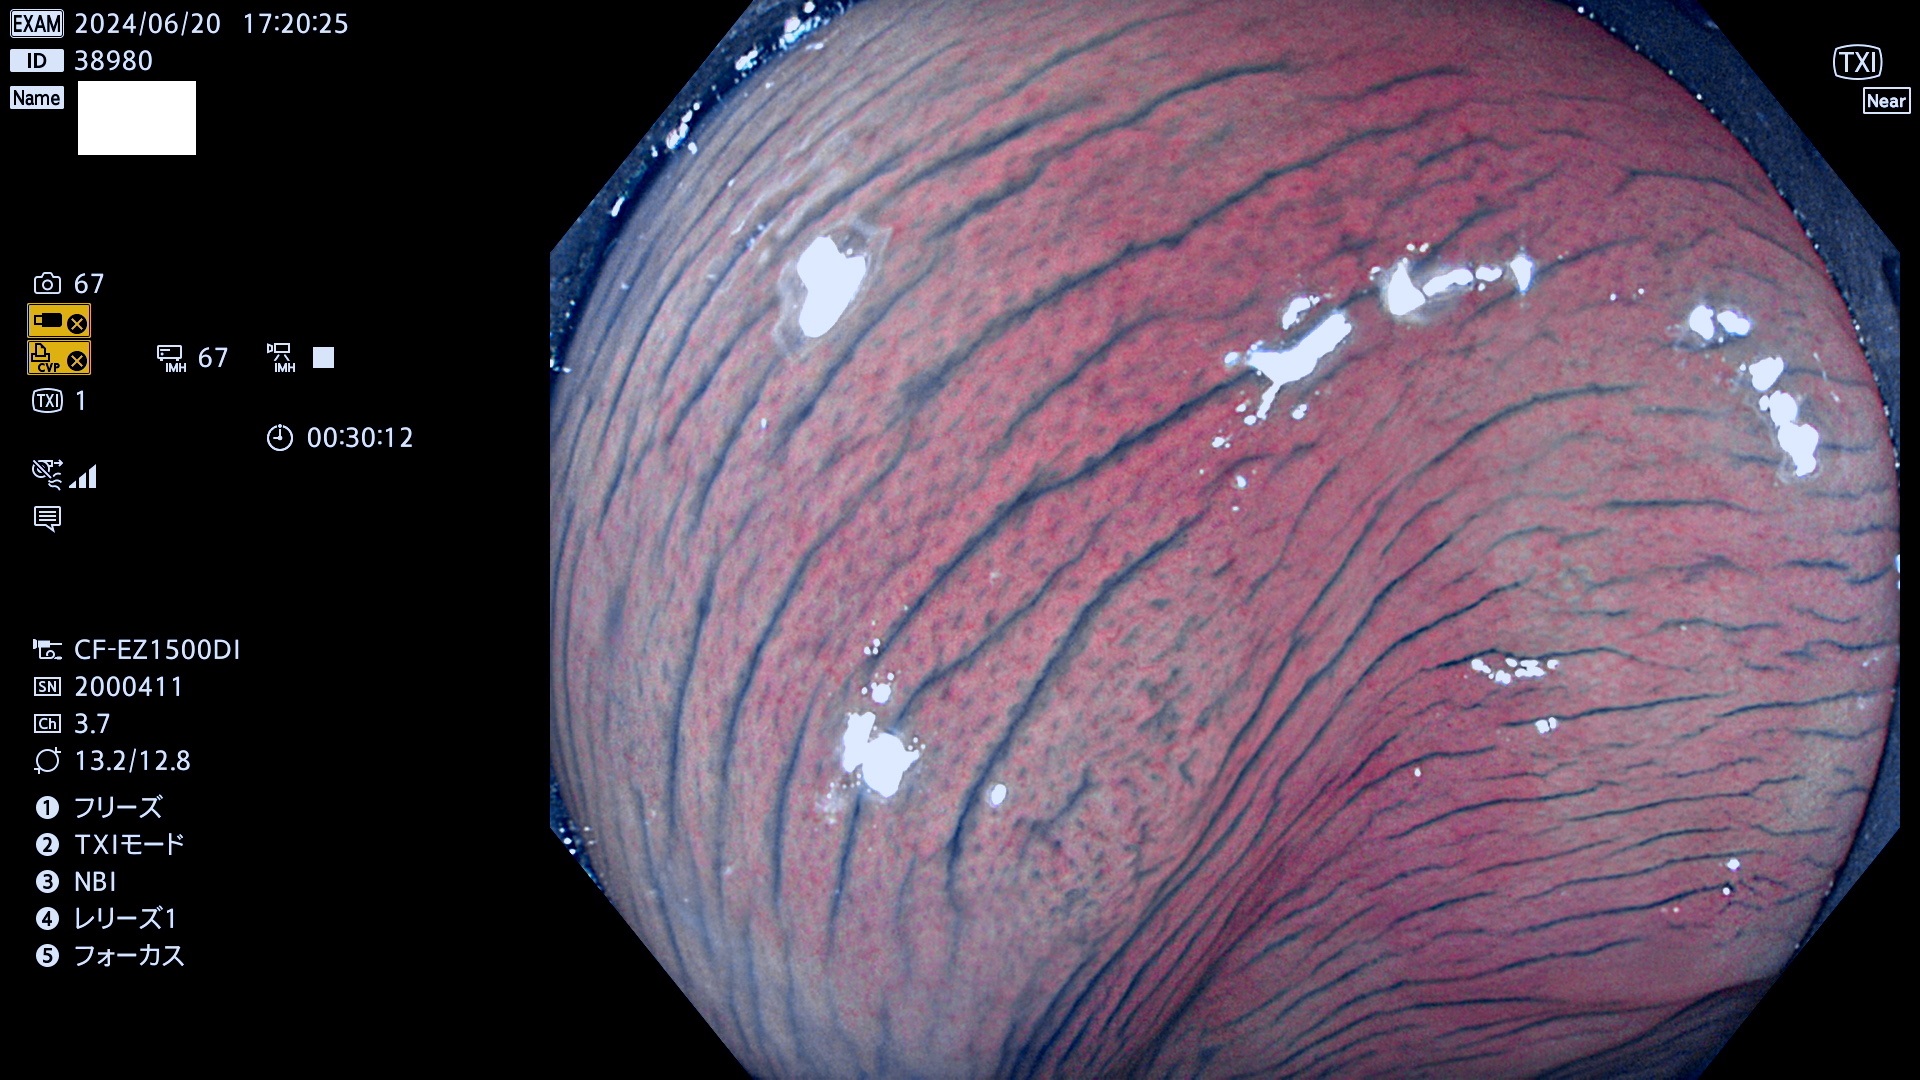

今週のUb、Uc型腺腫

完全に平坦な物をUb、陥凹している物をUcと呼びます。最も発見が難しく危険な病変です。

抽出の対象期間 2024年6月20日〜6月24の5日間(40件の検査)6件 (6/40=15%)